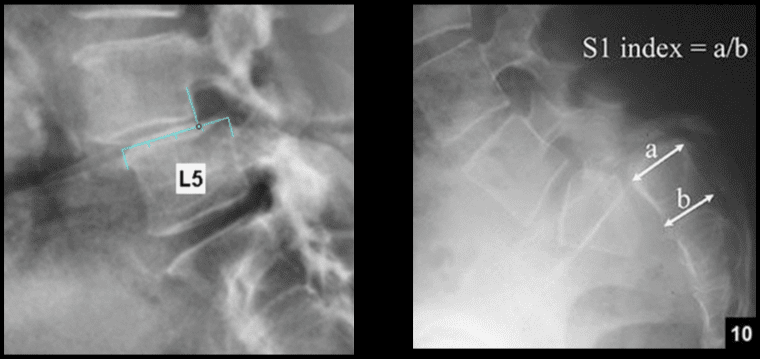

L-uġigħ u t-tenerezza lokalizzata fis-sinsla assjali ġeneralment toriġina min-nociceptors misjuba fid-diski intervertebrali, il-ġogi tal-faċċati, il-ġogi sacroiliac, id-dura tal-għeruq tan-nervituri, u l-istrutturi miofaszjali li jinsabu fl-ispina axial. Kif issemma fit-taqsimiet ta 'qabel, il-bidliet anatomiċi deġenerattivi jistgħu jirriżultaw fi tidjiq tal-kanal tas-sinsla msejjaħ stenożi spinali, żieda żejda ta' proċessi spinali msejħa osteofiti, ipertrofija tal-proċessi articulari inferjuri u superjuri, spondilolistesi, tixrid tal-ligumum flavum u herniation disk . Dawn il-bidliet jirriżultaw f'ġabra ta 'sintomi li hija magħrufa bħala claudication newroġenika. Jista 'jkun hemm sintomi bħal uġigħ fid-dahar baxx u uġigħ fir-riġlejn flimkien ma' tnemnim jew tingiż fis-saqajn, dgħjufija fil-muskoli, u qatra fis-saqajn. It-telf ta 'kontroll tal-musrana jew tal-bużżieqa jista' jissuġġerixxi l-imġieba tad-dahar tas-sinsla u hemm bżonn ta 'attenzjoni medika fil-pront biex jiġu evitati diżabilitajiet permanenti. Dawn is-sintomi jistgħu jvarjaw fis-severità u jistgħu jippreżentaw diversi estensjonijiet f'individwi differenti.

Studji dwar l-Immaġini

L-immaġini f'mard deġenerattiv tad-diska tintuża prinċipalment biex tiddeskrivi relazzjonijiet anatomiċi u karatteristiċi morfoloġiċi tad-diski affettwati, li għandha valur terapewtiku kbir fit-teħid ta 'deċiżjonijiet futuri għal għażliet ta' trattament. Kwalunkwe metodu ta 'immaġini, bħal radjografija sempliċi, CT, jew MRI, jista' jipprovdi informazzjoni utli. Madankollu, kawża sottostanti tista 'tinstab biss fi 15% tal-pazjenti billi l-ebda bidliet radjoloġiċi ċari ma huma viżibbli f'mard deġenerattiv tad-diska fin-nuqqas ta' ħernja tad-diska u defiċit newroloġiku. Barra minn hekk, m'hemm l-ebda korrelazzjoni bejn il-bidliet anatomiċi li dehru fuq l-immaġini u s-severità tas-sintomi, għalkemm hemm korrelazzjonijiet bejn in-numru ta 'osteofiti u s-severità ta' uġigħ fid-dahar. Bidliet deġenerattivi fir-radjografija jistgħu jidhru wkoll f'nies bla sintomi li jwasslu għal diffikultà biex jikkonformaw ir-rilevanza klinika u meta tibda l-kura. ("Marda tad-Diska Deġenerattiva" Fiżjopedja)

Ir-Radjografija